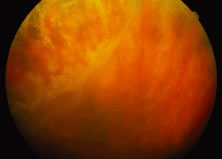

The ARN patient typically presents with progressive visual blurring in one or both eyes occurring over several weeks. These patients often are initially treated with corticosteroids, antitoxoplasmosis drugs, and other medications before arriving at the correct diagnosis. Examination reveals a prominent anterior uveitis that may be granulomatous or nongranulomatous (Fig. 1). Inflammatory signs may be prominent and cause severe pain (Fig. 2). The uveitis may be diffuse and so severe that it causes proptosis. These signs, and the diffuse vitreitis that makes the view of the retina difficult, may contribute to the high degree of delayed and/or misdiagnosis that occurs in the early stages of the disease. Significant vitreous cellular infiltration is seen in the presence of retinitis that is manifest by opacification of the retina, often most prominently in the periphery. Posterior pole involvement may include retinitis, as well as inflammation of the optic nerve head. Optic neuropathy might be the first sign of ARN with subsequent development of other retinal manifestations.8 Ultrasonography and computed tomography (CT) might be helpful in cases of ARN associated with optic nerve edema revealing enlargement of the optic nerve sheath.9 Even in ARN patients who are not immunocompromised and who have no clinical evidence of encephalitis, magnetic resonance imaging of selected cases has shown lesions of the lateral geniculate, optic tracts, and chiasma, which suggests that the virus spreads through the central nervous system (CNS) by axoplasmic transport from the retinal ganglion cells.10 A secondary retinal vasculitis is common, often accompanied by a mild number of retinal hemorrhages. Days to weeks after onset of the infection, the discrete peripheral lesions typically coalesce into a white or yellow ring of infected retina, and the associated vasculature is obliterated (Fig. 3). Necrotic retina desquamates into the vitreous resulting in vitreous sheets.3,6 Eventually, most untreated eyes can be expected to develop retinal detachment resulting from development of multiple full-thickness retinal breaks accompanied by traction or exudation.11 Giant retinal pigment epithelial tears have also been reported.12